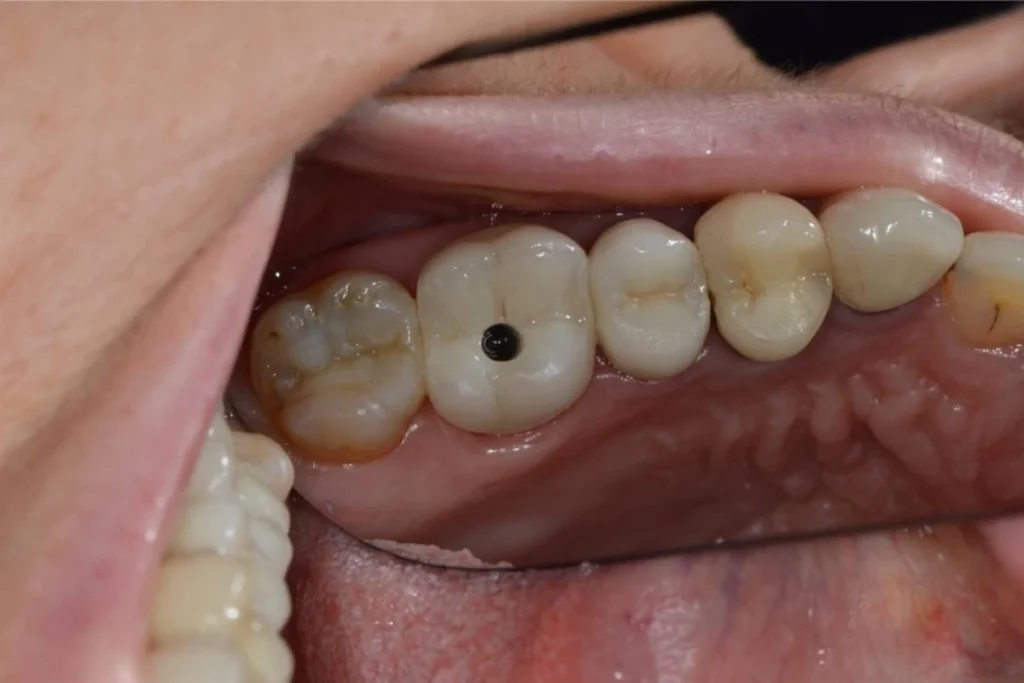

Nous vous présentons le cas de Mme B. 53 ans, qui consulte suite à des douleurs sur sa molaire supérieure gauche.

Après un examen clinique et radiographique, le verdict tombe… la dent n’est malheureusement plus conservable.

Après lui avoir exposé les différentes solutions, Madame B. souhaite remplacer sa dent par un implant. C’est la solution de choix pour retrouver une dent fixe sans avoir à abimer les dents de part et d’autre. L’analyse du scanner nous permet de proposer à Madame B. une extraction implantation immédiate. Il s’agit de réaliser en une seule et même séance l’extraction de la dent condamnée et la mise en place de l’implant dentaire.

Cela permet d’éviter une 2ème chirurgie à notre patiente et de raccourcir la durée du traitement de plusieurs mois. Un comblement osseux est réalisé le jour de l’intervention.

3 mois après la pose de l’implant, la patiente peut retrouver une dent fonctionnelle et esthétique.